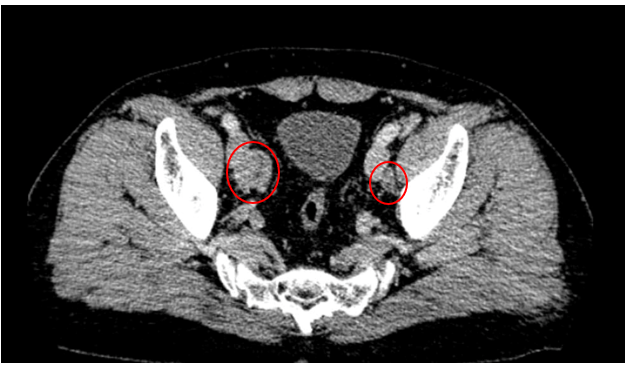

Hình 4: Hình ảnh nhiều hạch cạnh bó mạch chậu ngoài hai bên.